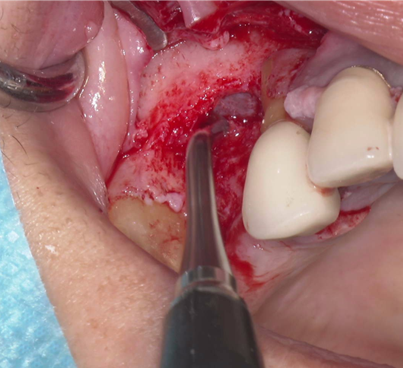

①歯槽頂よりサイナス

リフトを行いました。

②血液成分とカルシウム材料により骨造成をしました。